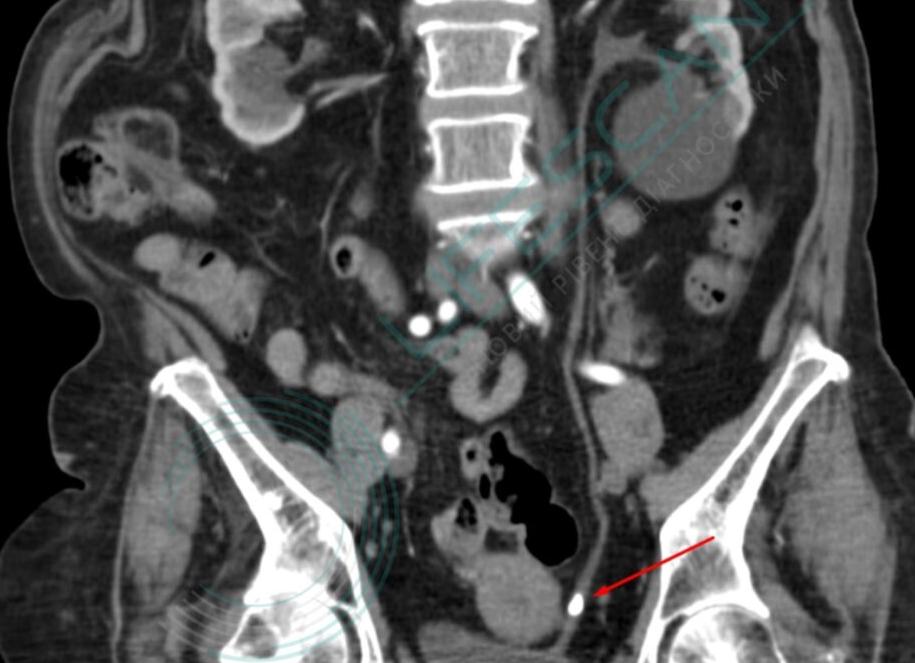

Кт забрюшинного пространства

КТ забрюшинного пространства — это метод исследования тканей с использованием рентгеновских лучей, при котором доктор получает послойное изображение нужных органов в заданной плоскости. Высокая точность и информативность этого метода исследования позволяет с большой вероятностью поставить верный диагноз и составить правильную схему лечения.